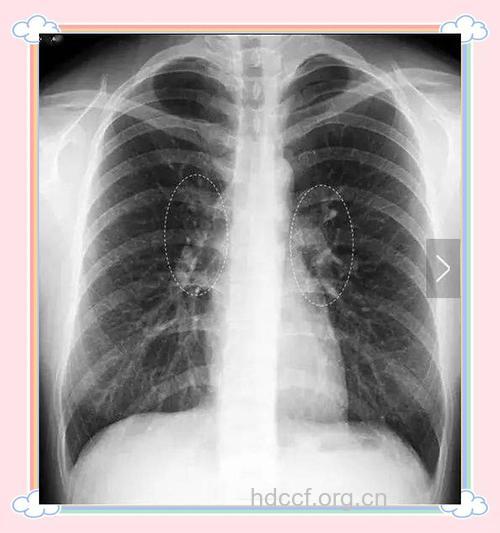

做体检一发现肺部有阴影,患者第一时间就怀疑是肺癌。实际上,肺部有阴影的话,有很多种可能,比如球形病灶,这种情况大约不到1/4的人是肺癌,剩下3/4的人可能是结核菌感染、真菌感染、肺包虫囊肿等五花八门的疾病。

另外,即便是肺部的GGO毛玻璃样病变,呈现模糊的、不规则的片状,手术切除,做病理检查也只有不到1/3是肺癌,绝大多数是肺结核、炎症感染等。